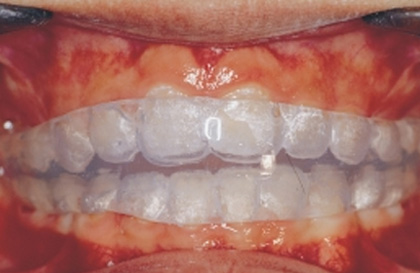

1. 牙齒細節調整器 ( Positioner )

由於矯正治療器本身之限制,排列剛結束之齒列,仍可能有少許缺陷。「牙齒細節調整器」是治療結束後初步使用的牙齒維護器。 該器是由矽膠製成 ; 它的製成,需專業矯正技師費時而精密的個人化設計與工作室操作,它可極度有效的在一個月內協助牙齒排列的更為良好。另外,它亦是個有效的牙齒維護器,它協助牙齒漸漸的穩定下來,達到健康且功能良好的平衡狀態。

牙齒細節調整定位器 ( Positioner ) 的使用方式:

◎ 第一個月您必須儘量全天候戴用它。除了進餐、刷牙與一些重要原因,您一天之內戴用的時間應超過20個小時 ; 戴用一個月後,醫師將會視病人不同的狀況調整配戴時間。